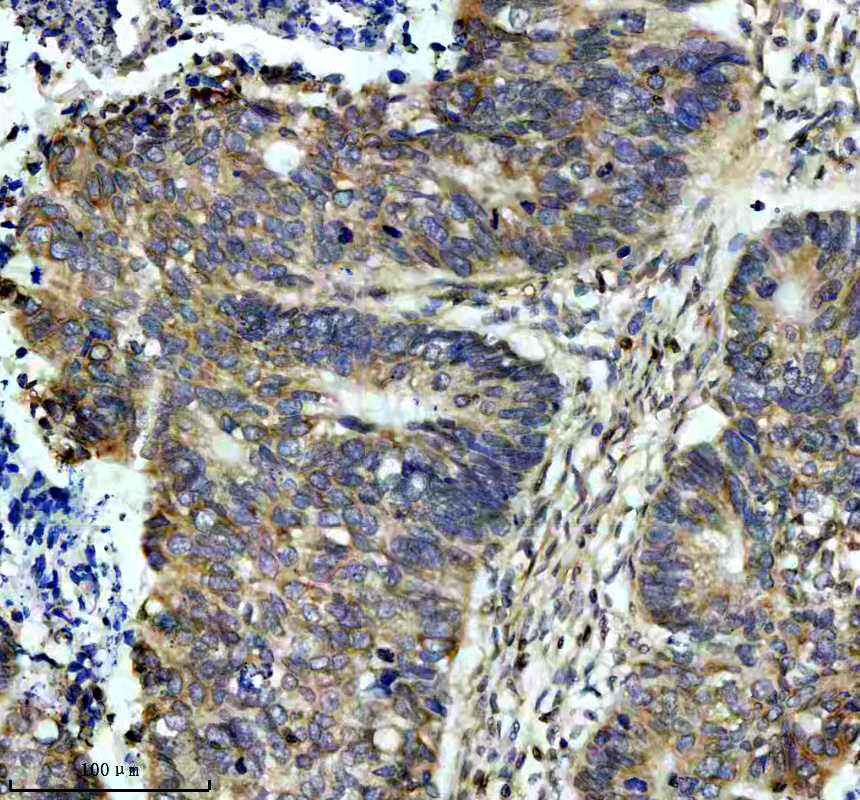

IHC analysis of CD95/FAS using anti-CD95/FAS antibody (BM4868) .

CD95/FAS was detected in a paraffin-embedded section of human colon cancer tissue. The tissue section was incubated with rabbit anti-CD95/FAS Antibody (BM4868) at a dilution of 1:200 and developed using HRP Conjugated Rabbit IgG Super Vision Assay Kit (Catalog # SV0002) with DAB (Catalog # AR1027) as the chromogen.